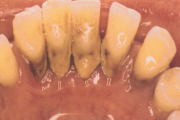

- igemed veritsevad (19)

- igemed punetavad (21)

- igemed on tursunud/vohavad (17)

- puudulik suuhügieen (5)

- igemepealne hambakivi (5)